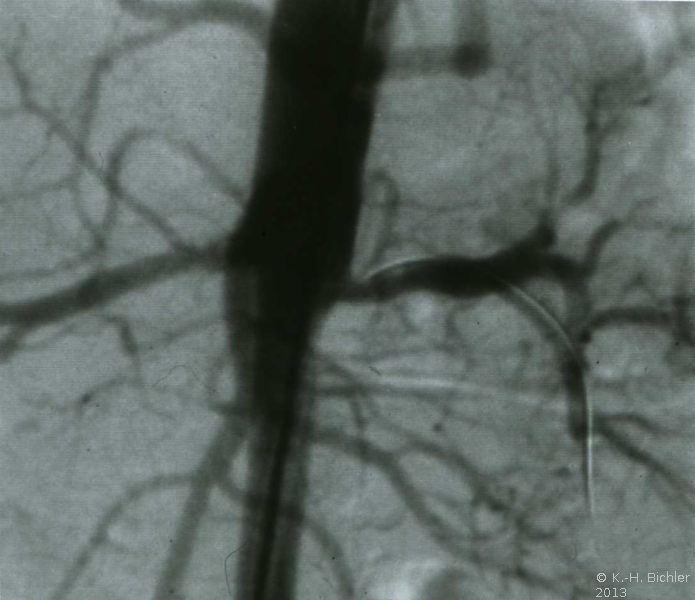

Die Röntgenübersicht der Niere und ableitenden Harnwege zeigten keinen Anhalt für Konkrement. Im Ausscheidungsurogramm eine "stumme Niere" links (Abbildung 19a). Bei der retrograden Sondierung links fand sich keine Abflussbehinderung (Stein oder Stenose) (Abbildung 19c). Im MCU kein Anhalt für Reflux (Abbildung 19b). Im Nierenfunktionsszintigramm MAG3 wurde eine seitengetrennte Funktionsverteilung von rechts zu links wie 93% zu 7% festgestellt. Zur Abklärung eventueller Gefäßalterationen erfolgte eine Renovasographie mit dem Nachweis einer langstreckigen Stenose der linken Arteria renalis (Abbildung 19d). Wegen des Verdachtes auf eine generalisierte Arteriitis wurden Angiographien weiterer Gefäßgebiete durchgeführt: Dabei fanden sich eine geringgradige Einengung der infrarenalen Aorta und der linken Arteria subclavia.